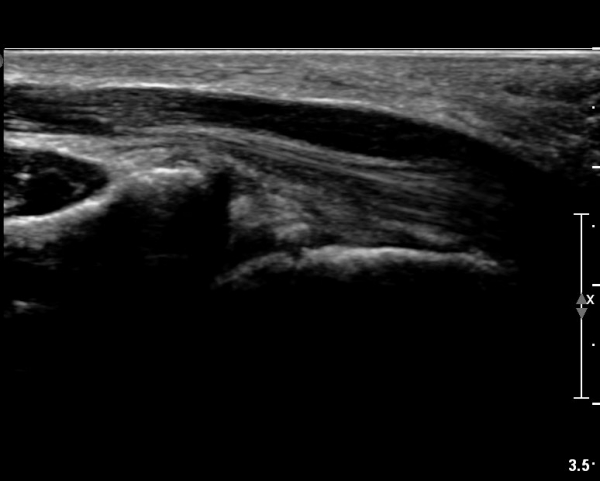

ÃÊÀ½ÆÄ ¼Ò°ß :  ¼Õ¸ñ±ÙÀ§ºÎ Ⱦ´Ü¸é°Ë»ç¿¡¼­ ¼Õ¸ñ±¼±Ù°Ç(FCR)°ú Ç¥Ãþ ¼Õ°¡¶ô ±ÁÈû±Ù(FDS) »çÀÌ¿¡

Á¤Á߽ŰæÀÌ Á¤»óÀûÀÎ ¾ç»óÀ¸·Î º¸ÀÓ(»çÁø 1).

Å½ÃËÀÚ¸¦ ¸»´ÜÀ¸·Î À̵¿ÇÏÀÚ  Á¤Áß½Å굥 ¿äÃø ÀϺΰ¡ Àú¿¡ÄÚ Á¾±«·Î °üÂûµÊ(»çÁø 2).

ÀÌ·± ¸ð½ÀÀº ¼Õ¸ñÀÇ ¿ù»ó°ñ ºÎÀ§(»çÁø 3, 4)¸¦ Áö³ª ¼ö±Ù°ü ±ÙÀ§ºÎ ±îÁö À̾îÁü(»çÁø 5).